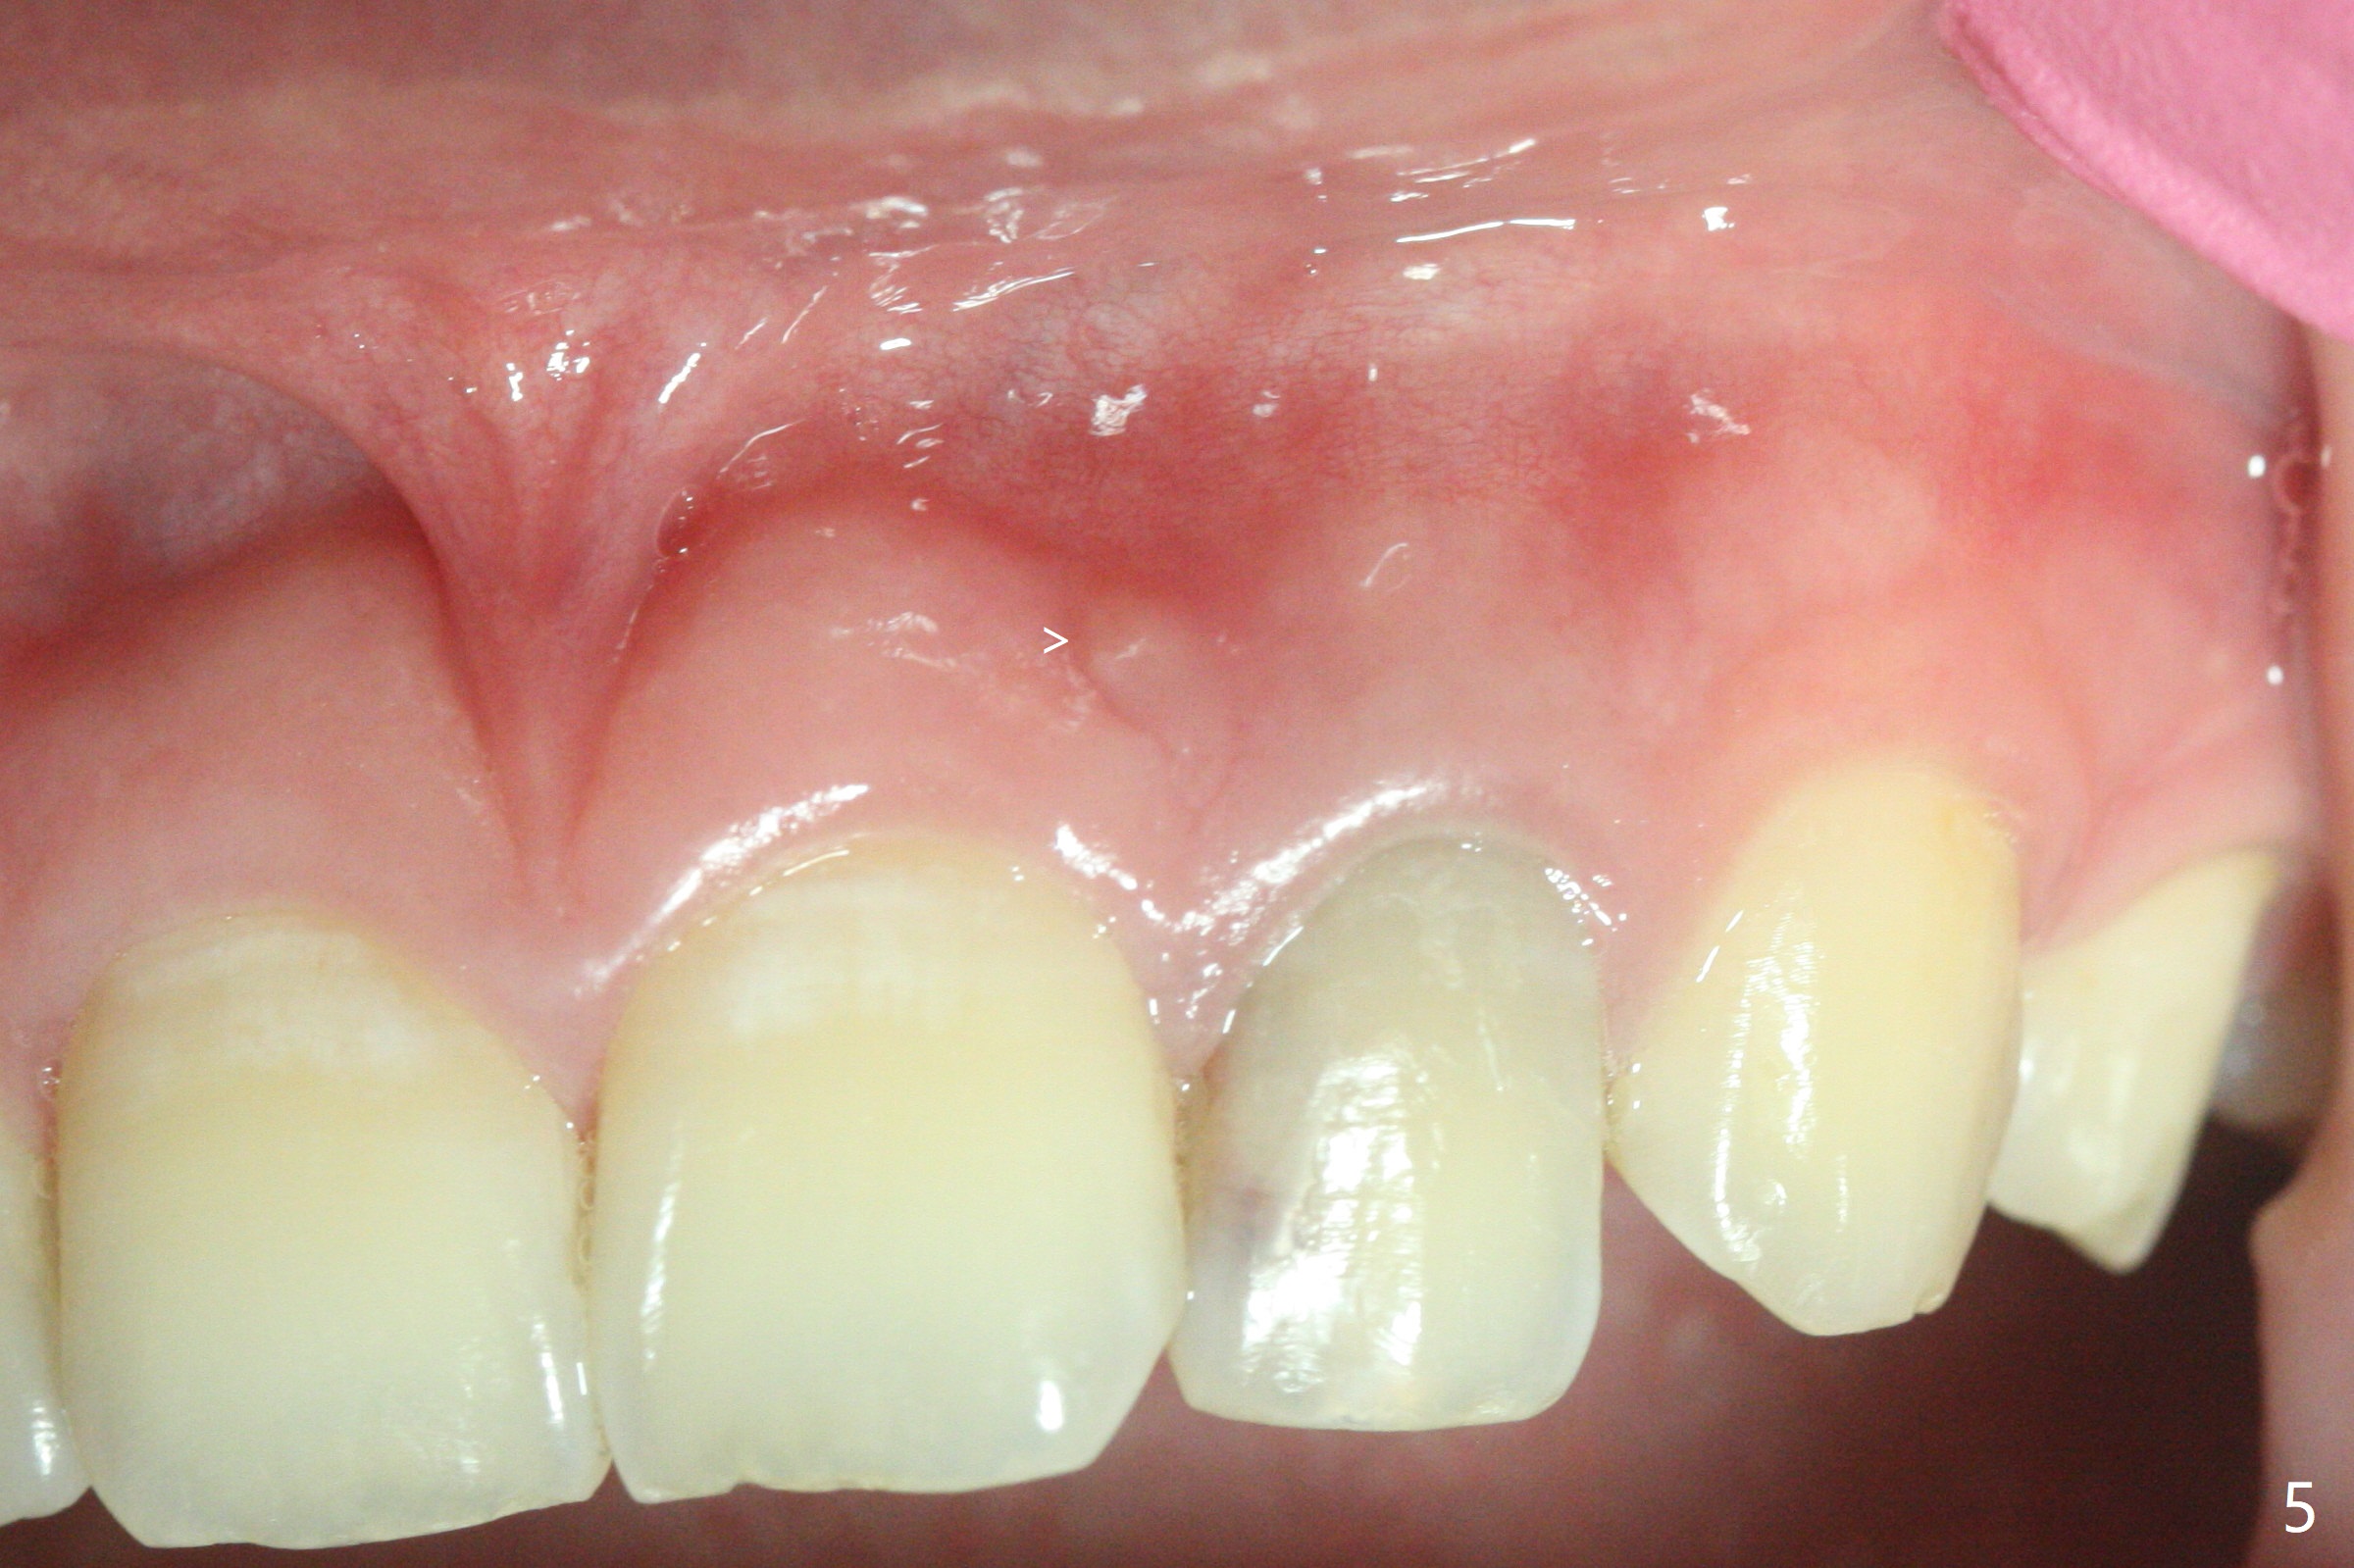

21岁女左上侧切牙根管治疗在别的诊所完成后出现瘘道(图一),近中阴影相当大(图二),应该如何处理?单独重做根管治疗足够吗?牙齿似乎没有松动,牙周袋正常,龋齿易感性高。牙列完整,仿佛没有咬合创伤迹象。可能由于经济问题,家长迟迟不带她去看专家。上个月我开始重做(图三:40/.04),能一次完成治疗吗?保险起见,放置氢氧化钙糊剂(图四)。一个月后病人回来,瘘道减小(图五),多次根管冲洗后,放置主牙胶尖(图六:40/.04),我当时在想根侧方阴影这么大,是不是有侧枝根管?如果扩根完善,根充时可能显示!是吗?其实这是最后根尖片(图七),40/.04主牙胶尖加三个fine, fine accessory gutta percha,并没有显示侧枝根管。